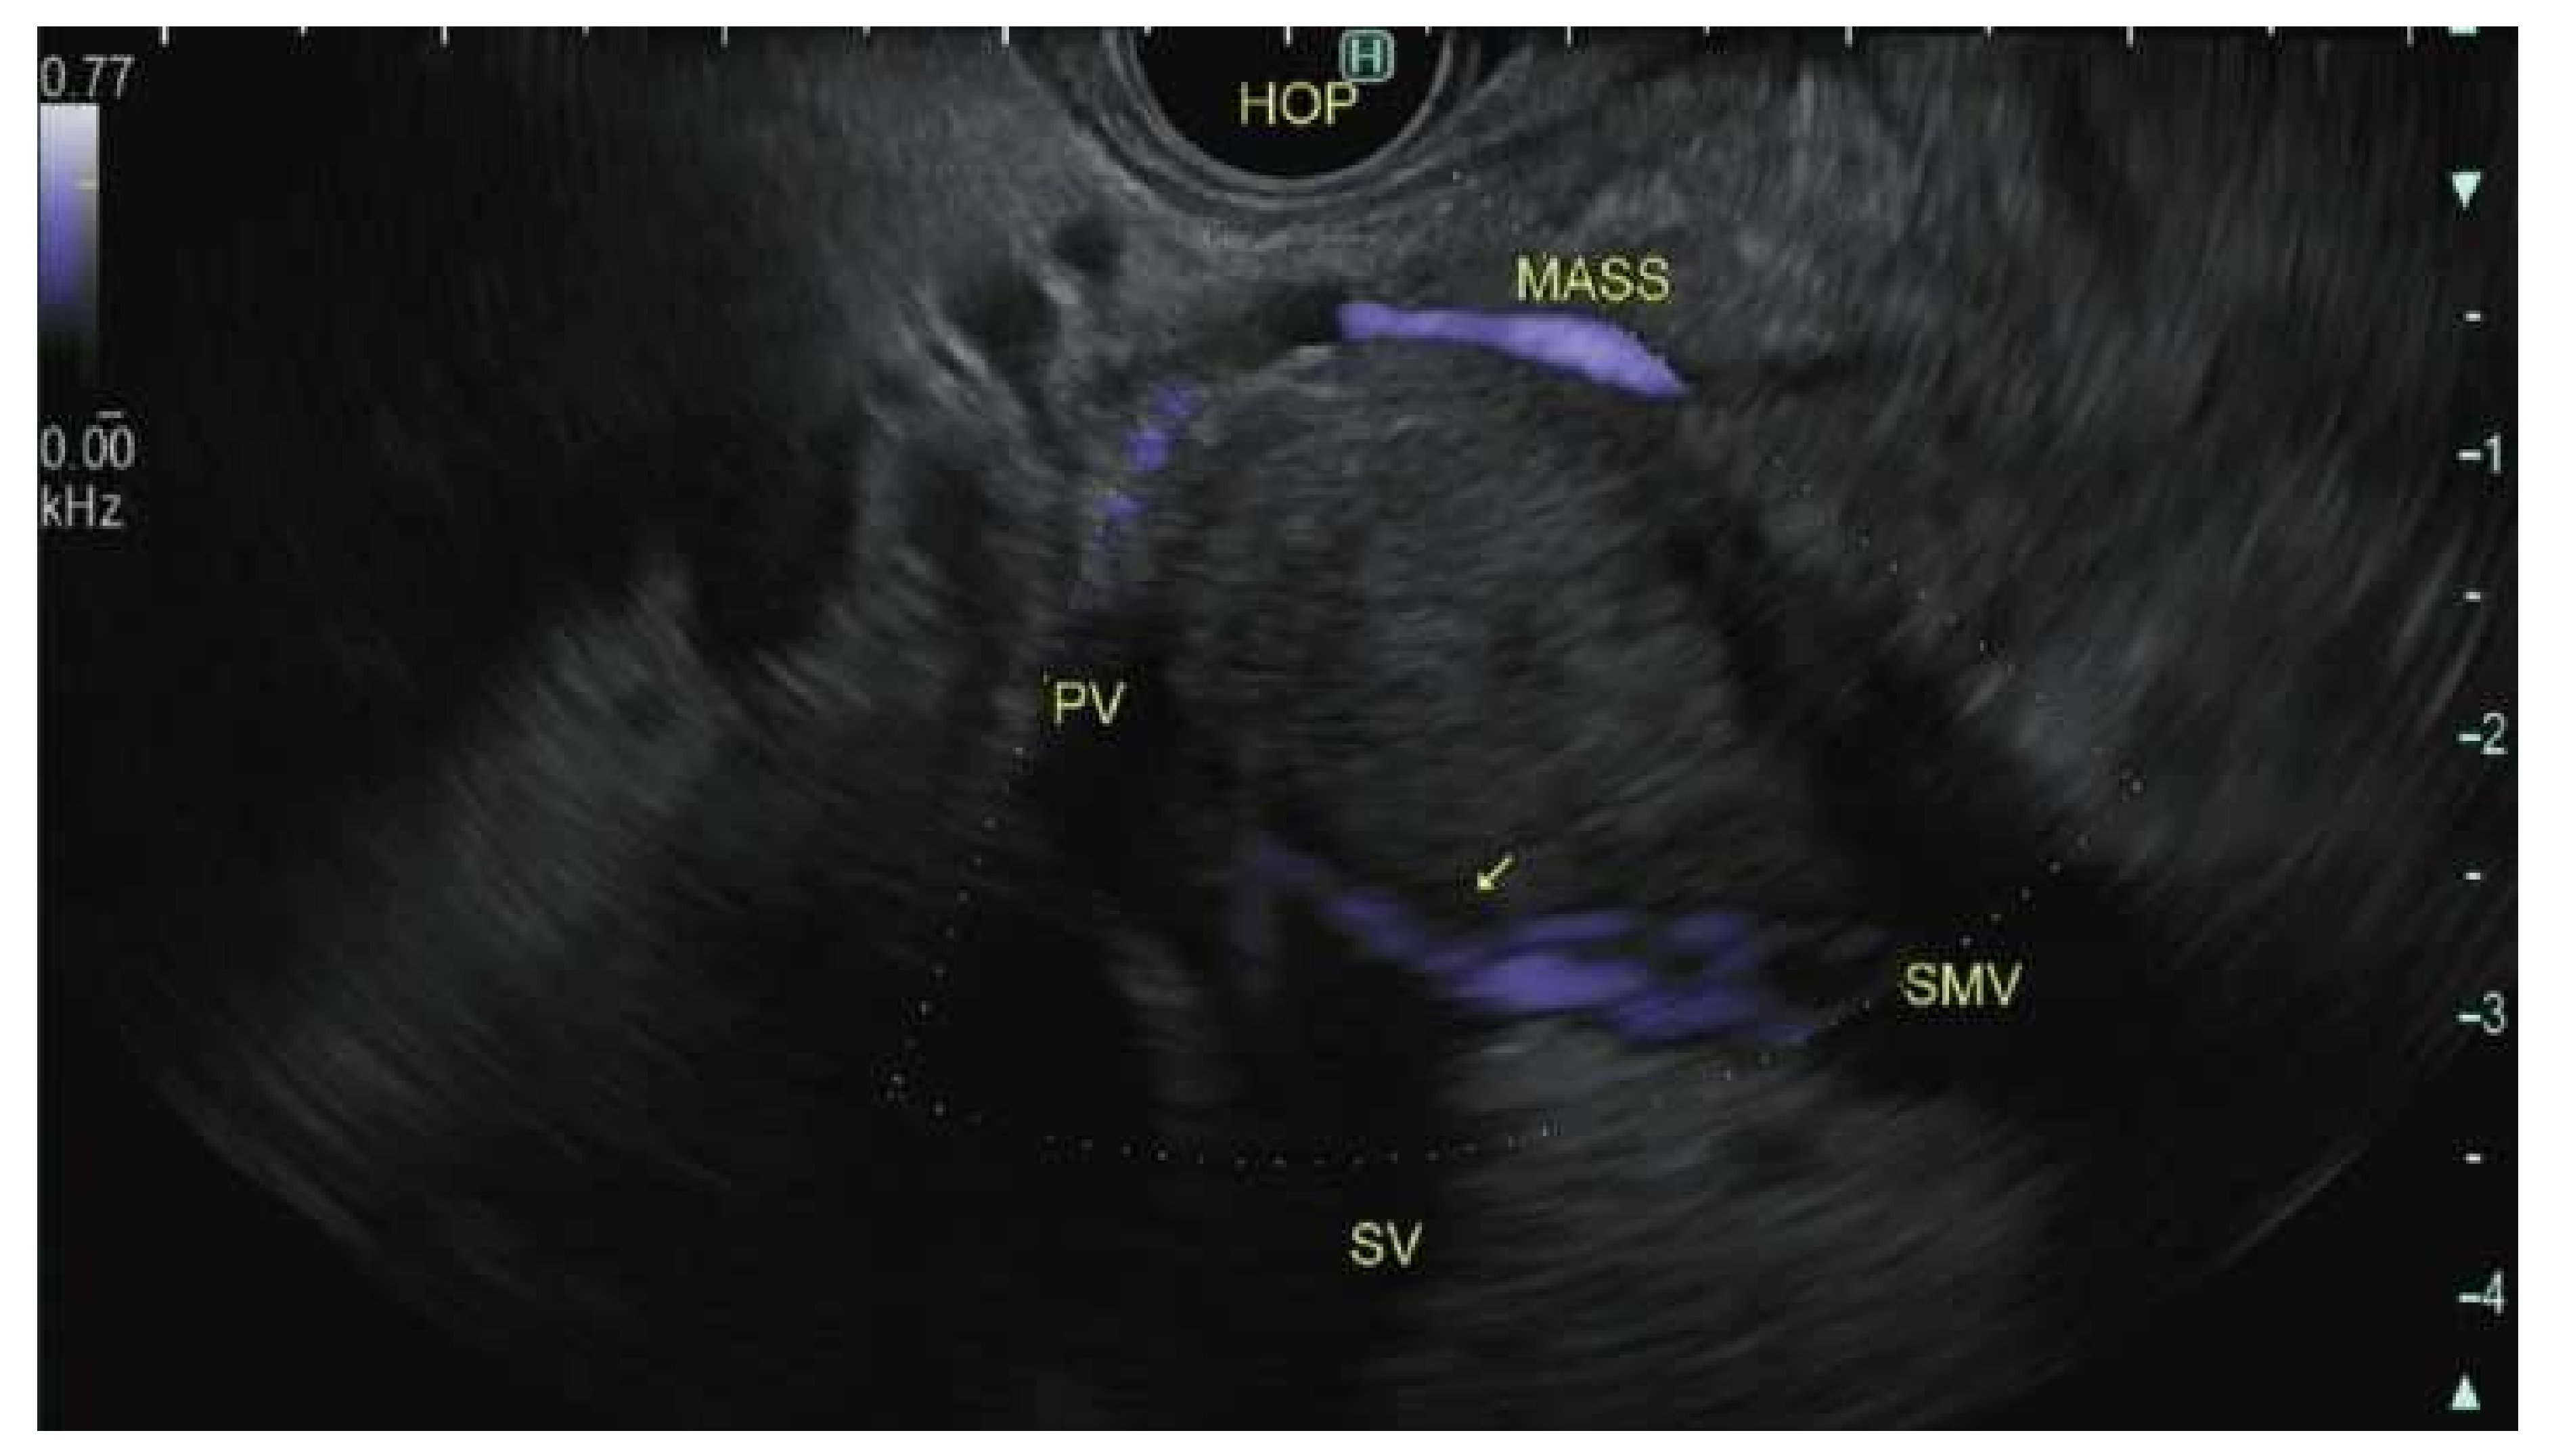

7. Staging

- An interface between the primary tumor and superior mesenteric vein portal vein (SMV-PV) measuring 180° or greater of the circumference of the vein wall, and/or

- Short segment occlusion of the SMV-PV with normal vein above and below the level of obstruction that is amenable to resection and venous reconstruction, and/or

- Short segment interface (of any degree) between tumor and hepatic artery with normal artery proximal and distal to the interface that is amenable to resection and arterial reconstruction, and/or

- An interface between the tumor and superior mesenteric artery (SMA) or celiac trunk measuring less than 180° of the circumference of the artery wall.

- Yang, R.; Lu, M.; Qian, X.; Chen, J.; Li, L.; Wang, J.; Zhang, Y. Diagnostic accuracy of EUS and CT of vascular invasion in pancreatic cancer: A systematic review. J. Cancer Res. Clin. Oncol. 2014, 140, 2077–2086. [Google Scholar] [CrossRef] [PubMed]

- Nawaz, H.; Fan, C.Y.; Kloke, J.; Khalid, A.; McGrath, K.; Landsittel, D.; Papachristou, G.I. Performance characteristics of endoscopic ultrasound in the staging of pancreatic cancer: A meta-analysis. JOP J. Pancreas 2013, 14, 484–497. [Google Scholar] [CrossRef]

- Rösch, T.; Dittler, H.-J.; Strobel, K.; Meining, A.; Schusdziarra, V.; Lorenz, R.; Allescher, H.-D.; Kassem, A.M.; Gerhardt, P.; Siewert, J.-R.; et al. Endoscopic ultrasound criteria for vascular invasion in the staging of cancer of the head of the pancreas: A blind reevaluation of videotapes. Gastrointest. Endosc. 2000, 52, 469–477. [Google Scholar] [CrossRef]

- Glazer, E.S.; Rashid, O.M.; Klapman, J.B.; Harris, C.L.; Hodul, P.J.; Pimiento, J.M.; Malafa, M.P. Endoscopic ultrasonography complements computed tomography in predicting portal or superior mesenteric vein resection in patients with borderline resectable pancreatic carcinoma. Pancreatol. Off. J. Int. Assoc. Pancreatol. (IAP) 2017, 17, 130–134. [Google Scholar] [CrossRef]